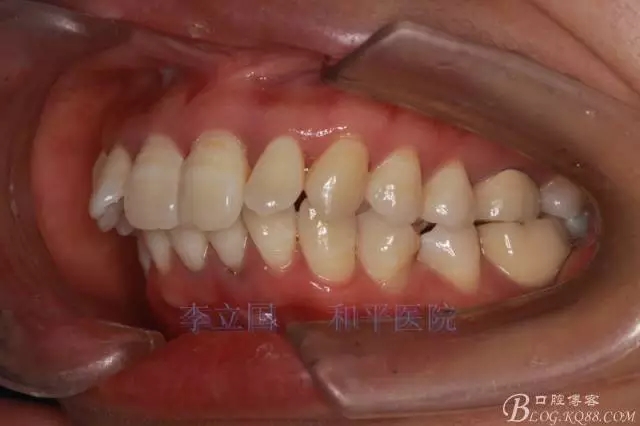

2.磨牙關(guān)系一側(cè)完全遠(yuǎn)中,一側(cè)遠(yuǎn)中尖対尖,采用兩個上4,一個下1的拔牙模式。

1.拔除14、24、31。